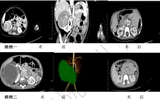

兰大二院小儿外科成功开展肾母细胞瘤保肾手术,守护患儿“肾”命健康与生活质量